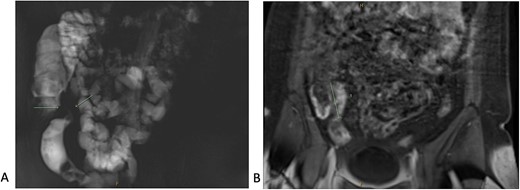

The patient proceeded to an elective laparoscopic ileocolic resection with a side-to-side stapled anastomosis. Macroscopically, there was a stricture of the proximal ileum with associated small bowel wall dilatation and ulceration and cobble stoning of the terminal ileum. Histopathology confirmed stricturing CD—with acute on chronic inflammation, fissuring ulcer formation, reactive epithelial hyperplasia, chronic inflammatory change and smooth muscle hypertrophy (Fig. 3). A second distinct stricture confirmed an endometriotic deposit in the muscularis externa and submucosa with associated haemosiderin-laden macrophages (Fig. 4). This was an unexpected finding of endometriosis in the terminal ileum, as there were no apparent endometrial deposits elsewhere at the time of laparoscopy.

Histopathological findings in CD; (A) H&E section (×20 magnification) showing fissuring ulceration, focal cryptitis, crypt abscess and background smooth muscle hypertrophy; (B) H&E section (×40 magnification) showing submucosal lymphoid aggregates and plasma cells; (C) H&E section (×200 magnification) showing Paneth cell metaplasia (arrows); (D) H&E section (×100 magnification) showing Nerve twig hypertrophy (arrows) at the base of the ulcer.